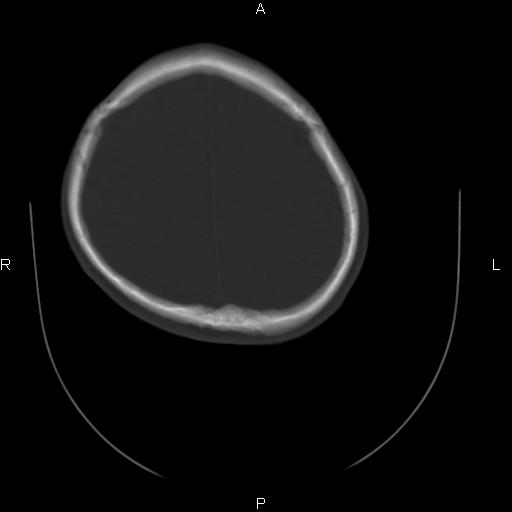

标题: CT27115:大家看一看,这孩子的颅骨表现? [打印本页]

标题: CT27115:大家看一看,这孩子的颅骨表现?

两名中学生打架,脑质内未见异常,未上传。

颅骨骨质未见异常。

颅骨未见骨折征象。

两例——颅骨结构正常,未见明显骨折征象。